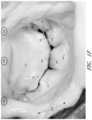

Turning now toFIGS.11A-11B and12A-12C, an embodiment of thecoaptation assistance device500 is shown withventricular hub864 engagingventricular anchor866 andannular eyelet862 engagingannular anchor863. Each anchor may be engaged at its proximal end by adriver870. InFIGS.11A,11B, and12B, the drivers are seen emerging fromplacement catheter872. It can be seen that in some embodiments, the device can be assembled extra-corporeally, engaging the anchors to the device and the drivers to the anchors. The drivers can then be withdrawn into the catheter, with the device in its collapsed position as shown inFIG.12A500. The drivers may be separately manipulated by the surgeon to place the anchors in the appropriate positions. Alternatively, the anchors may be engaged to the device and/or the driver sequentially, either before or after deployment through the catheter.FIG.11C illustrates the coaptation element after placement, entirely covering theposterior leaflet14 so that it coapts with theanterior leaflet12 during systole and, with the native anterior leaflet, maintains the valve seal at the annular ring.